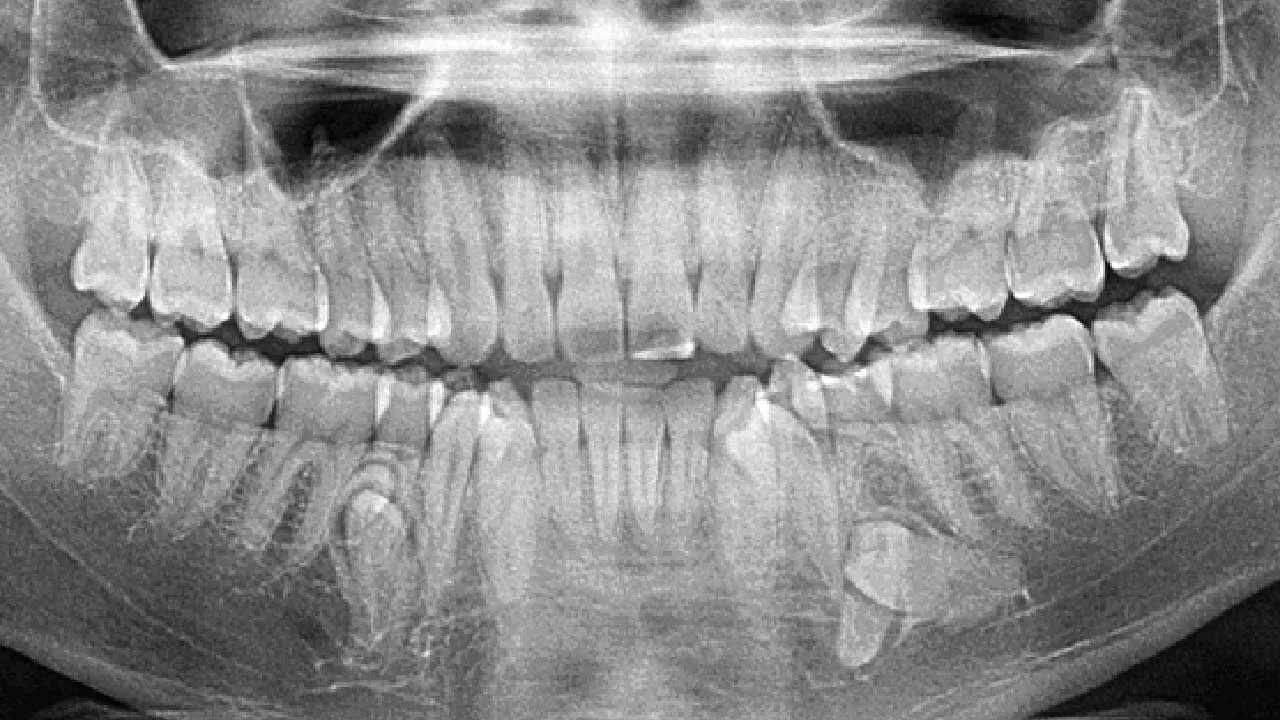

भारत में एक अनोखा विश्व रिकॉर्ड बना है। कल्पना बालन नाम की 26 वर्षीय महिला के मुंह में कुल 38 दांत हैं, जो एक सामान्य व्यक्ति से 6 अधिक हैं। इस उपलब्धि के कारण उनका नाम Guinness World Records में दर्ज किया गया है। ऐसे में सवाल उठता है कि यदि किसी व्यक्ति के मुंह में अतिरिक्त दांत हों, तो क्या उन्हें निकलवा देना चाहिए या रहने देना ठीक है?

सामान्यतः एक वयस्क व्यक्ति के मुंह में 32 दांत होते हैं। लेकिन कल्पना बालन के मुंह में नीचे के जबड़े में 4 और ऊपर के जबड़े में 2 अतिरिक्त दांत हैं। ये दांत किशोरावस्था में धीरे-धीरे उगने लगे थे। उन्हें विशेष दर्द तो नहीं होता, लेकिन खाना खाते समय अक्सर भोजन दांतों के बीच फंस जाता है।

इस स्थिति को Hyperdontia या supernumerary teeth कहा जाता है। इसमें सामान्य से अधिक दांत विकसित होते हैं। दुनिया में लगभग 3–4% लोगों में यह समस्या देखी जाती है।